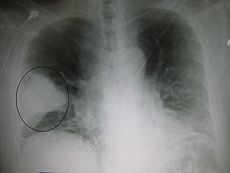

A chest radiograph is frequently used in diagnosis. In people with mild disease, imaging is needed only in those with potential complications, those who have not improved with treatment, or those in which the cause in uncertain. If a person is sufficiently sick to require hospitalization, a chest radiograph is recommended. Findings do not always correlate with the severity of a disease and do not reliably distinguish between bacterial infection and viral infection.

X-ray presentations of pneumonia may be classified as lobar pneumonia, bronchopneumonia (also known as lobular pneumonia), and interstitial pneumonia. Bacterial, community-acquired pneumonia, classically show lung consolidation of one lung segmental lobe which is known as lobar pneumonia. However, findings may vary, and other patterns are common in other types of pneumonia. Aspiration pneumonia may present with bilateral opacities primarily in the bases of the lungs and on the right side. Radiographs of viral pneumonia may appear normal, hyper-inflated, have bilateral patchy areas, or present similar to bacterial pneumonia with lobar consolidation. Radiologic findings may not be present in the early stages of the disease, especially in the presence of dehydration; or may be difficult to be interpreted in those who are obese or have a history of lung disease. A CT scan can give additional information in indeterminate cases.